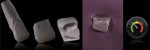

Posterior teeth chip for many reasons. The patient presented here cracked a tooth when chewing on a piece of ice (Figure 1). In order to restore the tooth back to its natural function and esthetics, dental technicians must always remember to study nature. When using refractory veneering techniques, the ceramic must always follow a natural build up. The dentin must be layered to the same contours observed in nature. Figure 2 illustrates how the dentinal cone was layered in the way nature intended. Dental professionals can understand this concept better by analyzing natural dentition that has been stripped of enamel using hydrochloric acid to show the underlying dentinal makeup.

Once the dentin layer has been properly applied (Figure 3), the enamel layer can be overlaid to create the natural composition of the previous cusp tip that had chipped away (Figure 4). Figure 5 shows the final outcome of the additive chip.